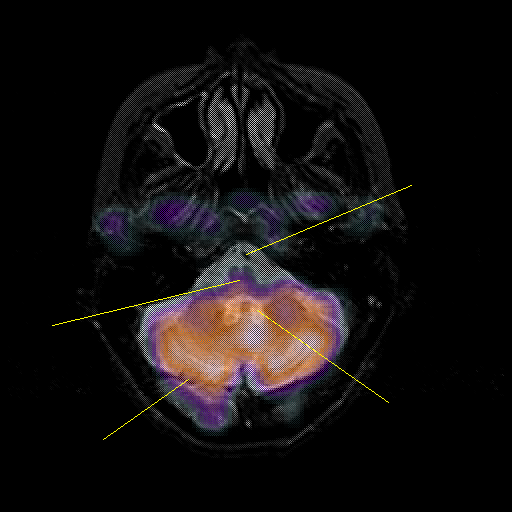

overlay : Slice 12

Slice 12

Pointers

Labeled